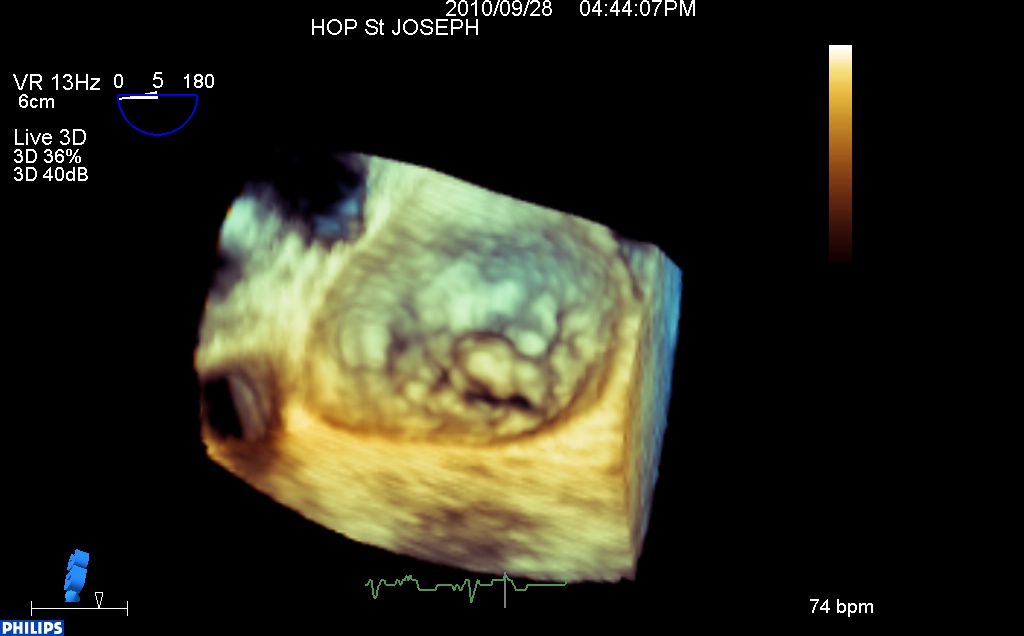

Vue 3D dite « chirurgicale », aorte en haut, auricule au gauche de l’écran, grande valve en haut avec un prolapsus médian et petite valve en bas :

Mitrale 3D from fish Nip echocardiographie on Vimeo.

Enfin, on note une dilatation et surtout une déformation importante de l’anneau (donc plutôt un type 1), qui est quasiment rond. Sur cette reconstruction tridimensionnelle de l’anneau en télésystole, les zones de restrictions paraissent en bleues, la zone prolabant (A2) est jaune. l’aorte est en haut, AL est la commissure antero-latérale.

Sur cette reconstruction 3D, on peut voir, dans le cadre en bas à droite, le petit carré bleu qui correspond au plan de l’anneau. Seul le A2 est au plan de l’anneau, le reste des feuillets sont en dessous, confirmant la restriction.